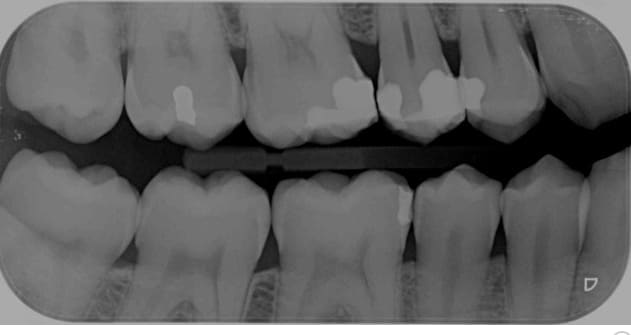

Sur la radio de Hokusai on voit combien de secteurs

18-17-16

17-16-15

16-15-14

3 secteurs DISTINCTS😀😀😀😀😀

Ici on peut voir 4 secteurs distincts de 3 dents contigues en rétro-coronaires aussi pourquoi pas.

18, 17, 16 - 16, 15, 14

48, 47, 46- 46, 45, 44

Je mets la définition de distinct pour que ca soit clair. Ces secteurs ne se confondent pas. -)

La notion de centre est primordiale. Une seule radio, un seul centre un seul secteur.

Sauf pour les rétro coronaires ou tu peux centrer sur 2 secteurs.

Ici tu ne peux coter que 2 secteurs de 1 a 3 dents contigues dents contigues. radio centrée sur 46 et 16 donc 2 secteurs distincts.

47,46,45 et 17,16, 15.